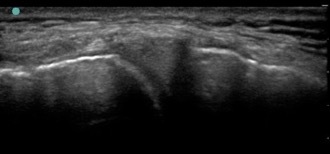

Knee Normal Meniscus Image